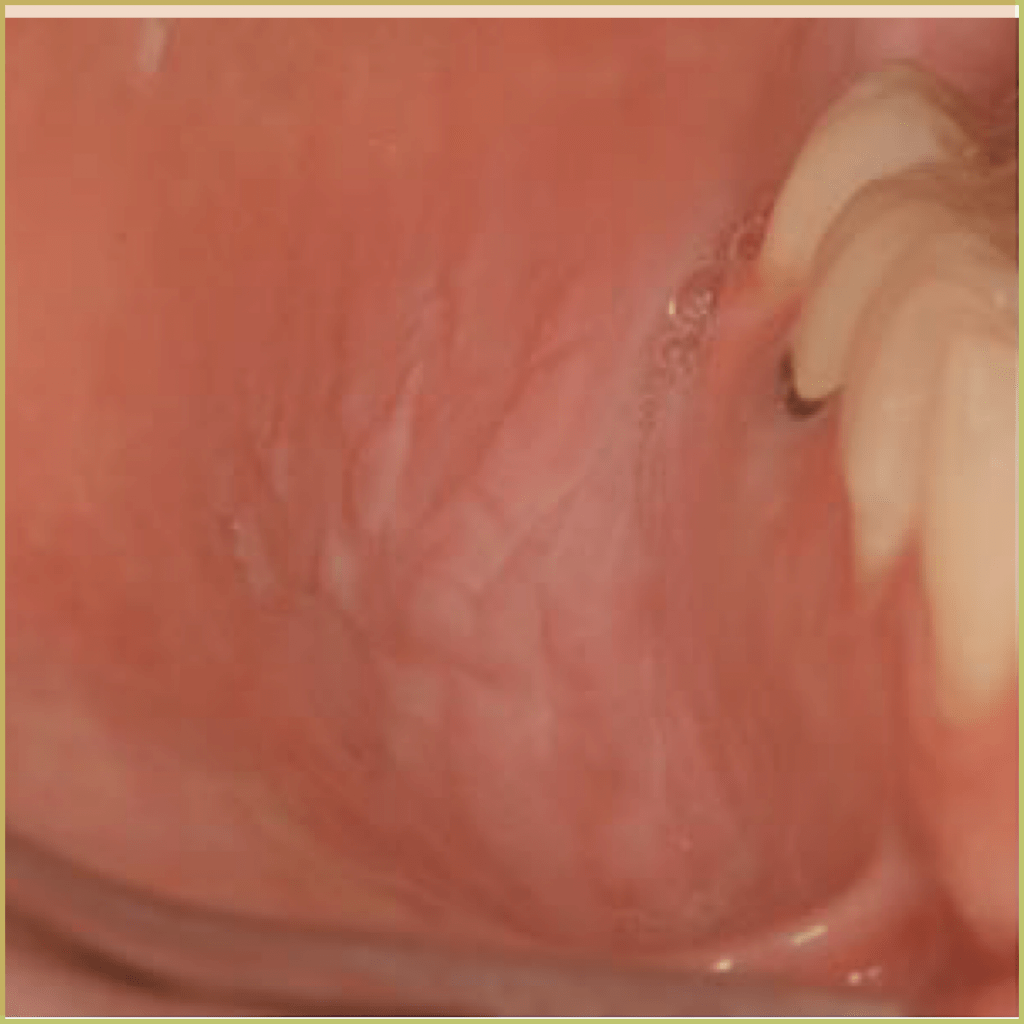

LICHEN PLANUS

Lichen Planus (Wickham striae) is a chronic inflammatory autoimmune disease that can affect the skin, nails, hair and mucous membranes. Oral lichen planus affects 3-4% of the population and is typically characterized by the presence of distinct reticular white lesions. The cause is not well understood but thought to involve the targeting of basal keratinocytes by activated T Cells. Clinical variations include erosive/ulcerative, papular, plaque-like, atrophic and bullous lesions. Multiple types may be found in the same patient and even in the same lesion. The common clinical presentation includes:

- Asymptomatic reticular lace-like patterns is the most common appearance.

- Most often located on the buccal mucosa, then tongue, gingiva and lips.

- Bilateral, often symmetrical distribution.

- Erosive or atrophic pattern can present with symptoms (pain or burning)

- Extra-oral lichen planus may accompany oral presentation (planar (flat-topped), purple, polygonal, pruritic, papules, and plaques).

- Higher incidence in white females and more likely in the fourth to eighth decade.

Diagnosis is based on the lesion history, clinical presentation and microscopic findings, which may include:

- Hyperkeratosis.

- Liquefactive degeneration of the basal layer of the epithelium.

- Presence of Civatte bodies (apoptotic keratinocytes).

- Band-like appearance of inflammatory infiltrate (lymphocytes) in the mucous membranes beneath the epithelium.

- No epithelial dysplasia.

- Saw tooth rete ridges.

Your differential diagnosis should include:

- Lichenoid drug reactions.

- Lupus erythematosus.

- Mucous membrane pemphigoid.

- Erythema multiforme.

- Contact stomatitis.

Reticular oral lichen planus does not require treatment and does not progress to a more serious disease. For symptomatic lesions, immune-suppressing agents can be utilized. Treatment options include:

- Topical corticosteroids for mild to moderate cases.

- Systemic prednisone for more severe cases.

- Topical tacrolimus ointment.

Though treatment does not provide a cure, long term control can be established. The prognosis is generally good with very rare malignant transformation.